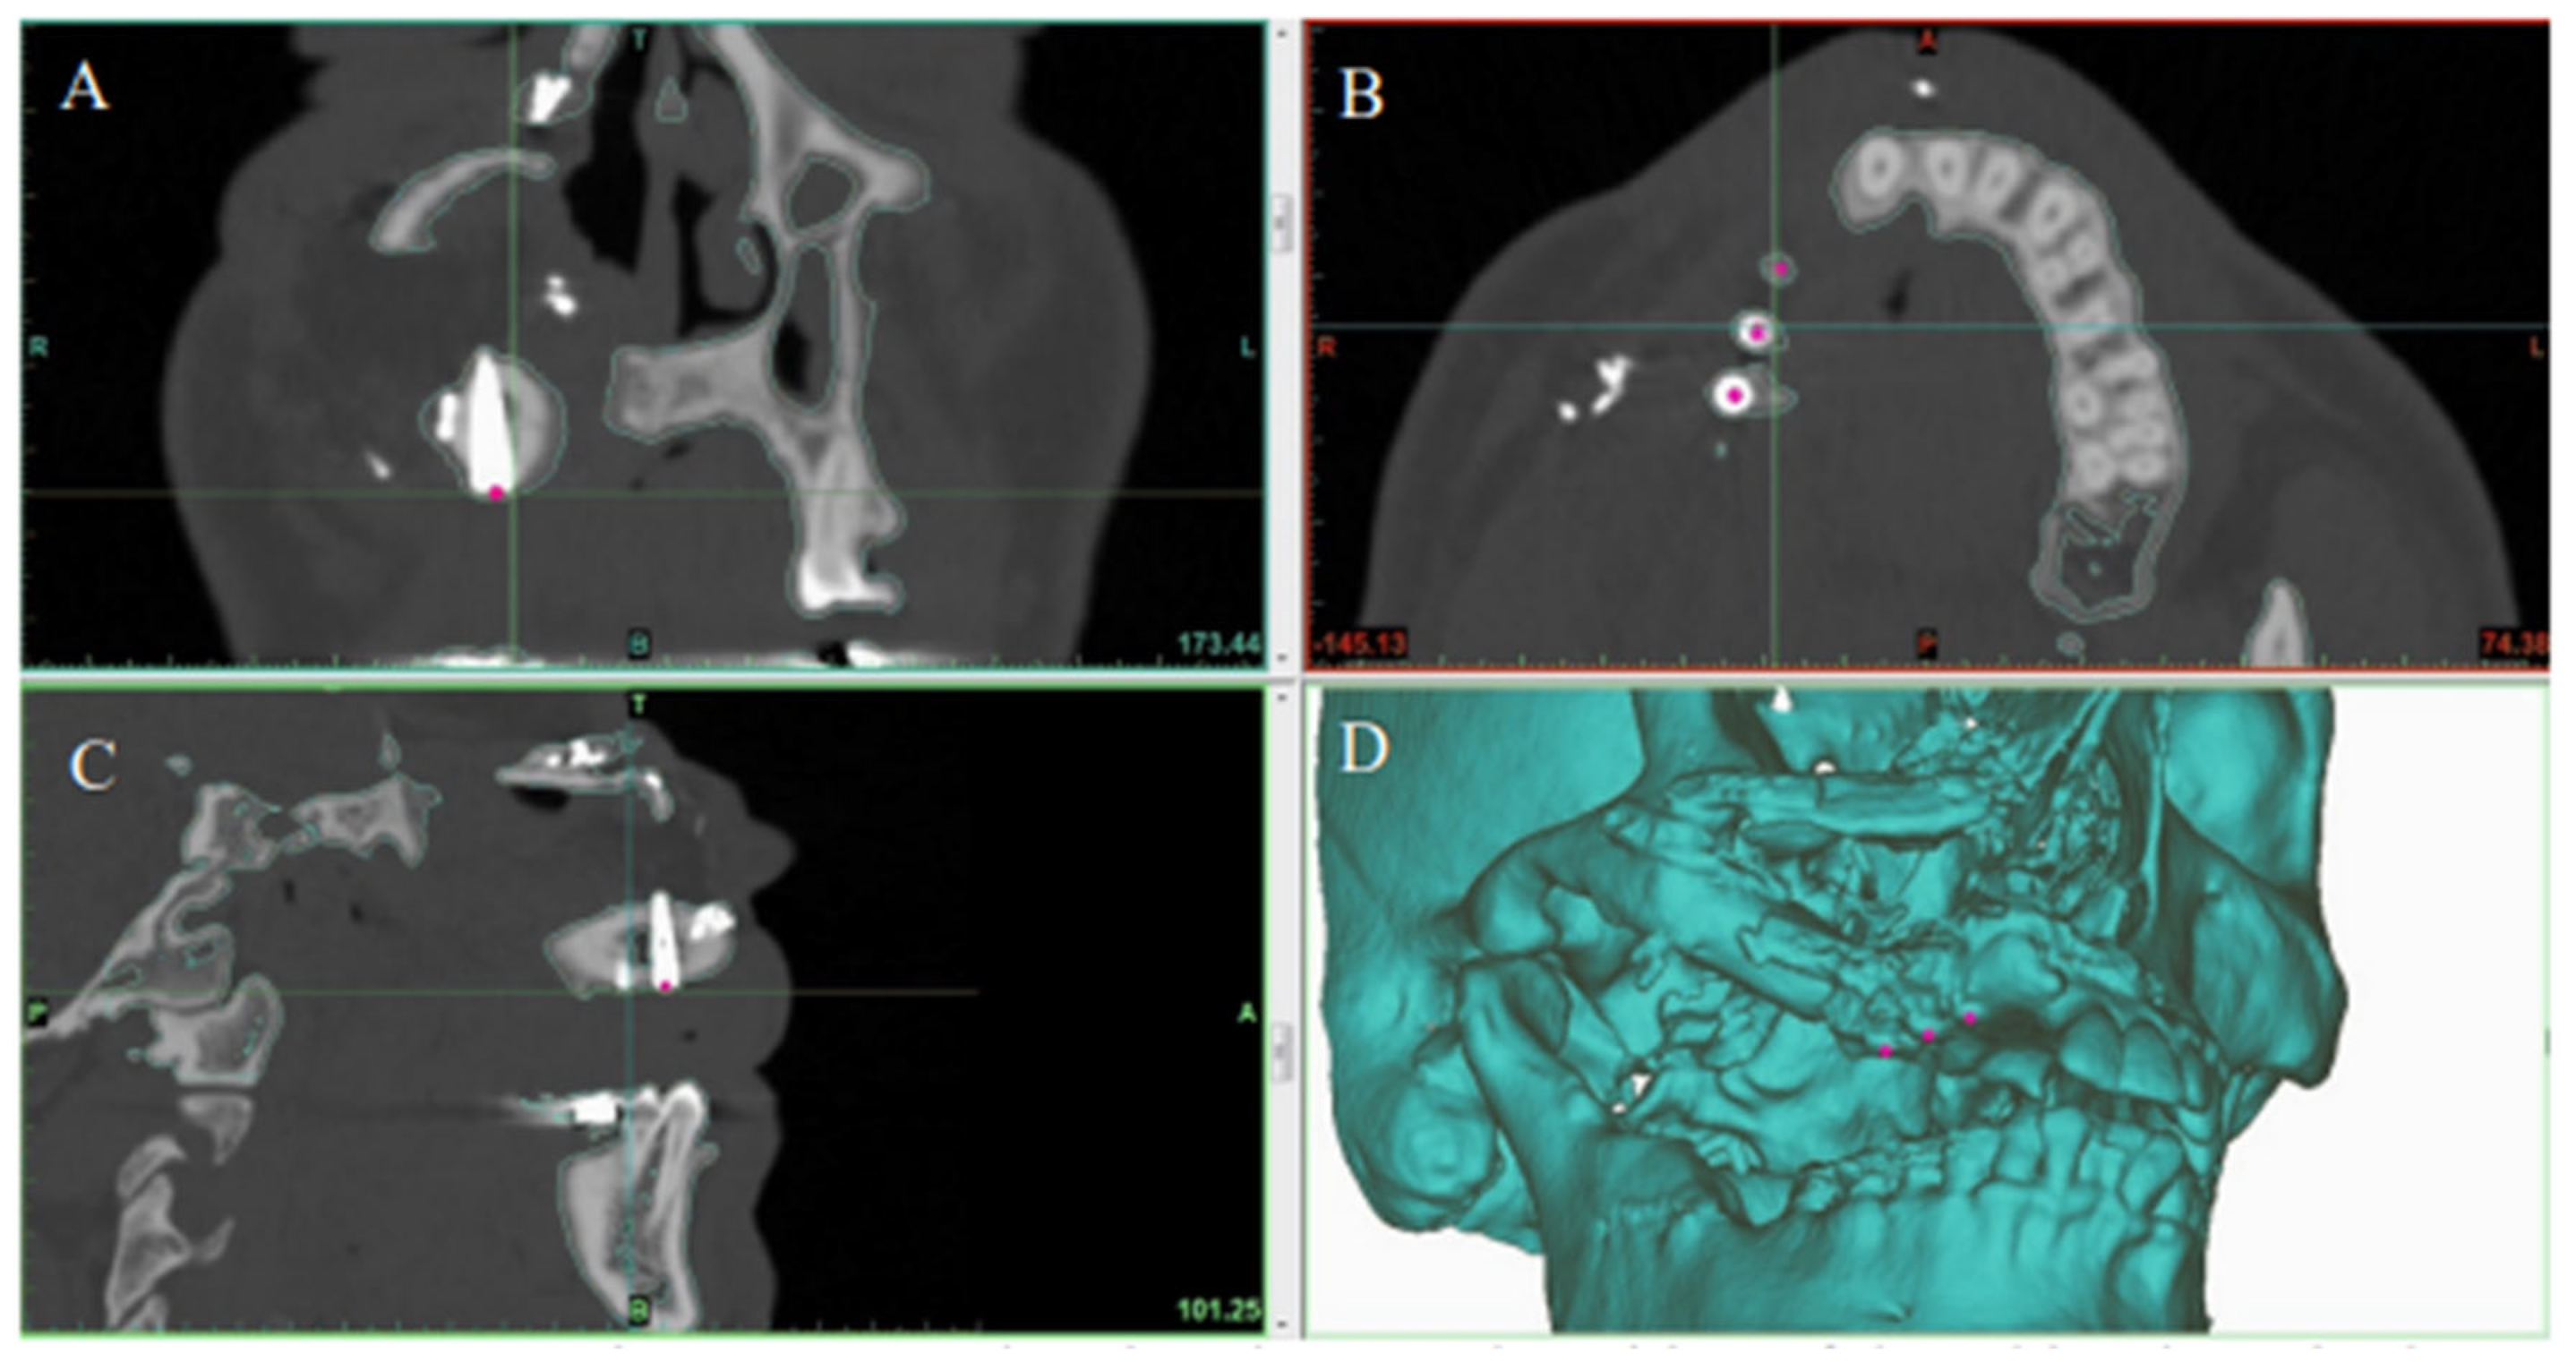

2.3. Virtual Surgical Planning

2.4. Surgical Procedure

2.4.1. Stage I: Flap Prefabrication

2.4.2. Stage II: Jaw Reconstruction